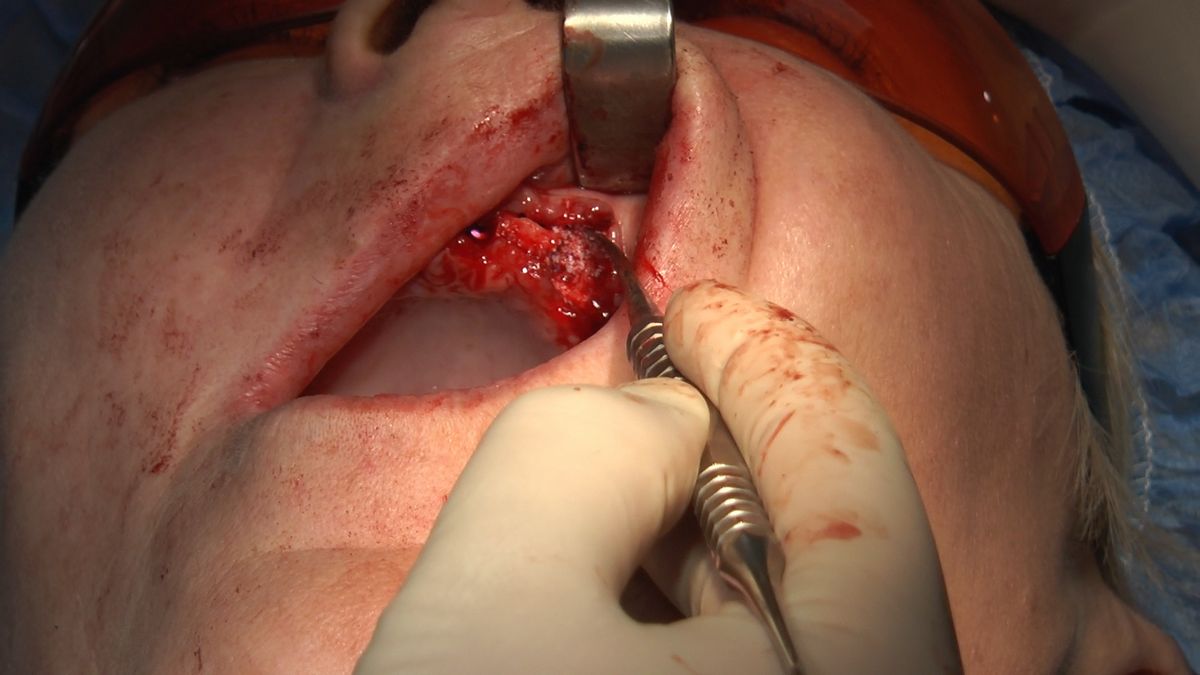

W ostatni weekend czerwca 2018 roku kursanci II Sezonu Preludium Implantologii odbyli piątą, finałową sesję, która w całości podporządkowana była praktyce. W ciągu dwóch dni zabiegowych Lekarze uczestniczący w szkoleniu przeprowadzili szereg zabiegów pod kierunkiem dr n.med. Violetty Szycik. Wszczepili 17 implantów oraz przeprowadzili ekstrakcje i zabiegi regeneracyjne kości. Zabiegi były wykonywane także w sedacji dożylnej z udziałem specjalisty anestezjologii i intensywnej terapii dr Jolanty Grzybowskiej. Preludium implantologii to nowy program edukacyjny dla adeptów implantologii stomatologicznej, którego celem jest wprowadzenie do implantologii poprzez pozyskanie wiedzy w szerokim zakresie i uwzględnieniem szczegółów mających decydujące znaczenie dla powodzenia leczenia implantologicznego. Ale tak jak wszystkie szkolenia w Instytucie Vivadental, w tym wiodące Practiculum Implantologii, zorientowane jest na praktyce i samodzielnym wykonywaniu zabiegów pod kierunkiem Mentora. To najlepsza edukacja w medycynie zabiegowej, a zarazem najlepszy start do implantologii.